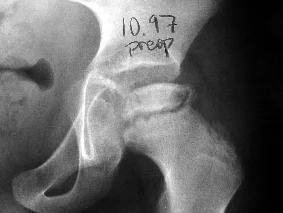

A continuación temas de interes ortopédico relacionados con la cadera.

Displasia   evolutiva de la cadera   Enfermedad de Legg Calve Perthes (enlace de interes)               Cojera en el niño

Dolores del crecimiento   Displasia evolutiva de la cadera. Caso clínico     Atroplastia total de cadera